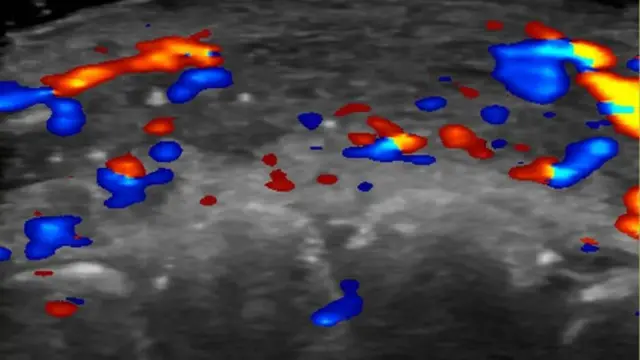

څېړونکو د هغو ۱۰۰ ناروغانو د معاینې لپاره د الټراساؤنډ (Ultrasound) د عکس اخیستنې ټیکنالوژي وکاروله چې د فیلر له تزریق وروسته یې ناغوښتل شوې پایلې لیدلې وې.

اوسمهال کلینیکونو ته سپارښتنه کیږي چې د فیلر د تزریق پرمهال نږدې شریانونو ته د زیان رسېدو مخنیوي لپاره، د دې عکس اخیستنې له ټیکنالوژۍ کار واخلي.

د برازیل د ساو پاولو پوهنتون د سیګریست یوې څېړنډلې په سلو (۱۰۰) ناروغانو کې د فیلر له امله رامنځته شوي د رګونو اختلالات ګډوډي وڅېړله. د الټراساؤنډ معایناتو ښودلې چې له نیمایي په کمه برخه کې په مخ کې د سطحې او ژورو شریانونو ترمنځ په کوچنیو رګونو کې د وینې جریان نه و، او نږدې په دریمه برخه کې په لویو رګونو کې د وینې جریان زیانمن شوی و.

سیګریست وايي: "که چیرې الټراساؤنډ د لارښود په توګه ونه کارول شي، نو د تزریق عملیات یوازې د کلینیکي معایناتو پر بنسټ ترسره کېږي، چې دا بې پلانه د تزریق عملیات ترسره کول دي." هغه زیاتوي چې "که موږ هغه څه وینو چې الټراساؤنډ یې راښيي، نو دا موږ سره مرسته کوي چې درملنه د بندېدو دقیق ځای ته را په ګوته کوي." هغه دې ته هم اشاره کوي، دې پرځای چې ټوله برخه د "هیالورونایډیز" (Hyaluronidase) په درملو ولړل شي ترڅو فیلر لرې کړي، متخصصین کولی شي په پام کې نیول شوي تزریقونه ترسره کړي چې کمه اندازه ماده کاروي او درملنې ته ښې پایلې ورکوي.